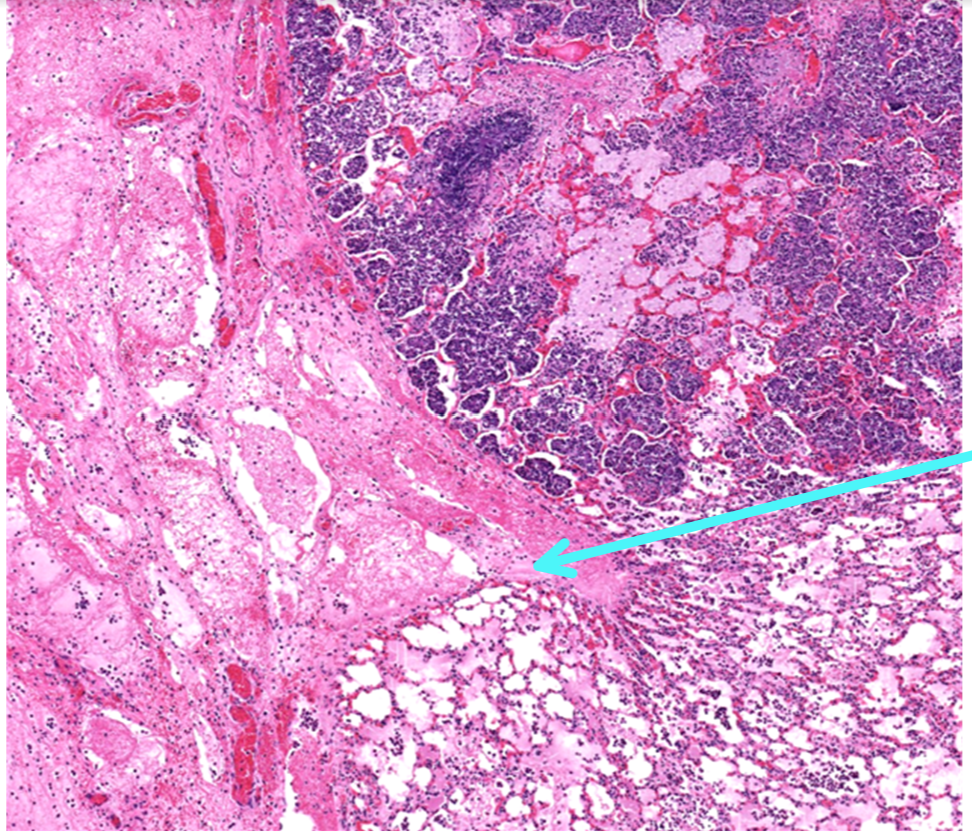

This is a slide from a bovine lung.What would the cellular exudate be composed of in this lesion?

macrophages, neutrophils, and necrotic alveolar epithelium

This is from a bovine lung. What is the histomorphologic diagnosis for this lesion?

acute fibrinopurulent bronchopneumonia

Identify this structure:

neutrophils

fibrin

Q

interlobular lymphatics with fibrin and hemorrhage

fibrin thrombi